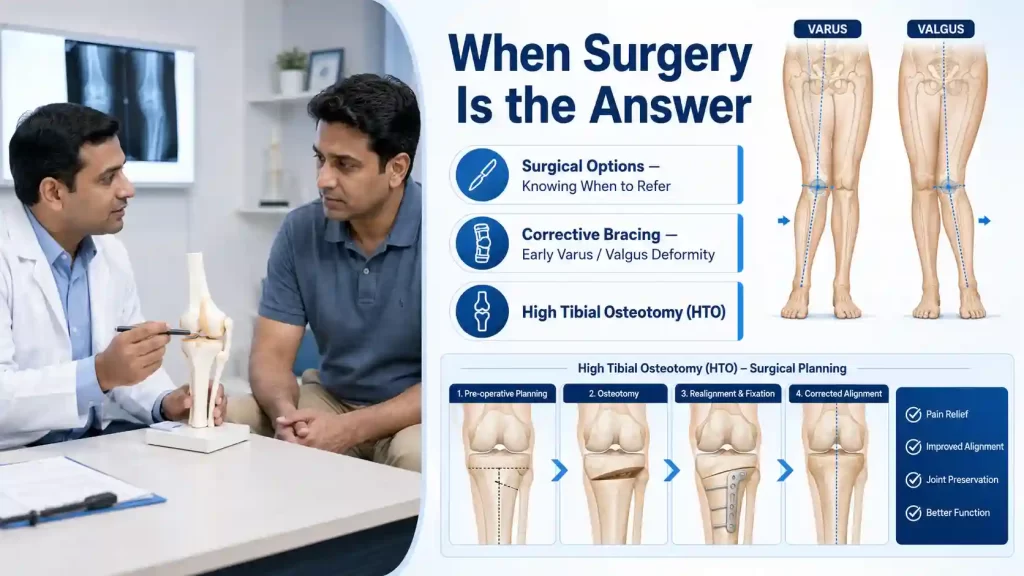

IBAP Clinics is not an anti-surgery practice we are a pro-appropriate-surgery practice. Our expertise lies in ensuring that patients receive the right intervention at the right time. Surgery is the correct answer for certain patients at certain stages and our role is to get them there in the best possible condition, or to delay that time as long as is clinically safe and patient-appropriate.

When KL Grade II–III OA is accompanied by early varus (“bow-leg”) or valgus (“knock-knee”) deformity, an offloading knee brace can shift mechanical load away from the damaged compartment, slowing disease progression and reducing pain. IBAP co-ordinates specialist brace prescription and review as part of the conservative management plan.

In younger, active patients with unicompartmental (one-sided) OA and significant varus or valgus malalignment, a high tibial osteotomy surgically realigns the leg — redistributing weight to the healthier cartilage compartment. This buys 10–15 years before a potential replacement is needed, and is the ideal surgical option for patients aged 35–55.

For end-stage OA (KL Grade IV) with bone-on-bone contact, significant deformity, and failure of all conservative treatments, total knee arthroplasty (TKA) or unicompartmental knee replacement (UKR) restores anatomy and dramatically improves quality of life. Surgical outcomes are now excellent modern implants have a 95% 15-year survival rate.

Our Surgical Referral Network: IBAP Clinics maintains collaborative relationships with leading orthopaedic surgeons in Hyderabad. When surgery is indicated, we provide a warm referral with full clinical documentation and continue to manage the patient’s pain perioperatively and postoperatively.